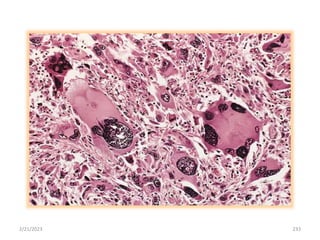

2/21/2023 233

2/21/2023 234